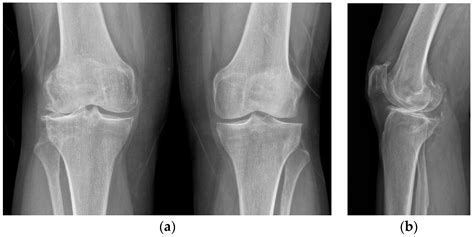

Tricompartmental degenerative arthrosis specifically affects the knee joint, which is divided into three compartments: the medial (inner), lateral (outer), and patellofemoral (front) compartments. When all three compartments are affected, it is termed tricompartmental. This condition is more common in older adults but can also occur in younger individuals due to injury or genetic predisposition.

Diagnosis of Tricompartmental Degenerative Arthrosis

Diagnosing tricompartmental degenerative arthrosis involves a combination of medical history, physical examination, and diagnostic tests. The diagnostic process typically includes:

• Imaging Tests: X-rays, MRI, or CT scans may be ordered to visualize the joint and assess the extent of cartilage damage.